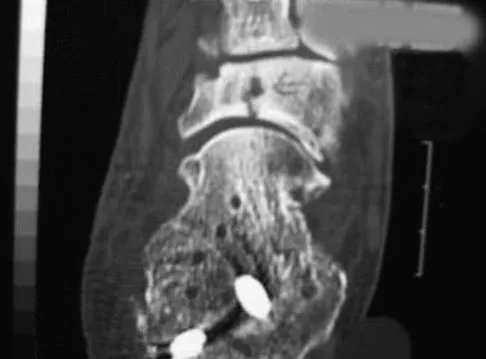

An 18-year-old gymnast has had a 1-year history of foot pain. Examination reveals medial midfoot tenderness without swelling. Non-weight-bearing in a cast for 6 weeks has failed to provide relief. An axial CT scan of the midfoot is shown in Figure 20. What is the optimal treatment for this condition?

Explanation